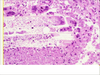

Candida bronchopneumonia

Candida